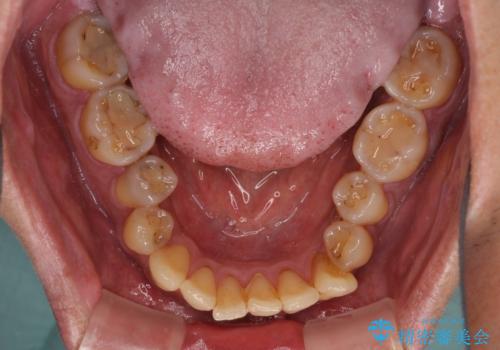

前歯のクロスバイトを改善 ワイヤー装置での非抜歯矯正

- 骨格的な咬み合わせのズレ、前歯のデコボコとクロスバイトを気にして来院された患者様です。

上下の叢生は速やかに改善できましたが、右側のクロスバイトの改善に1年以上の期間を要しました。